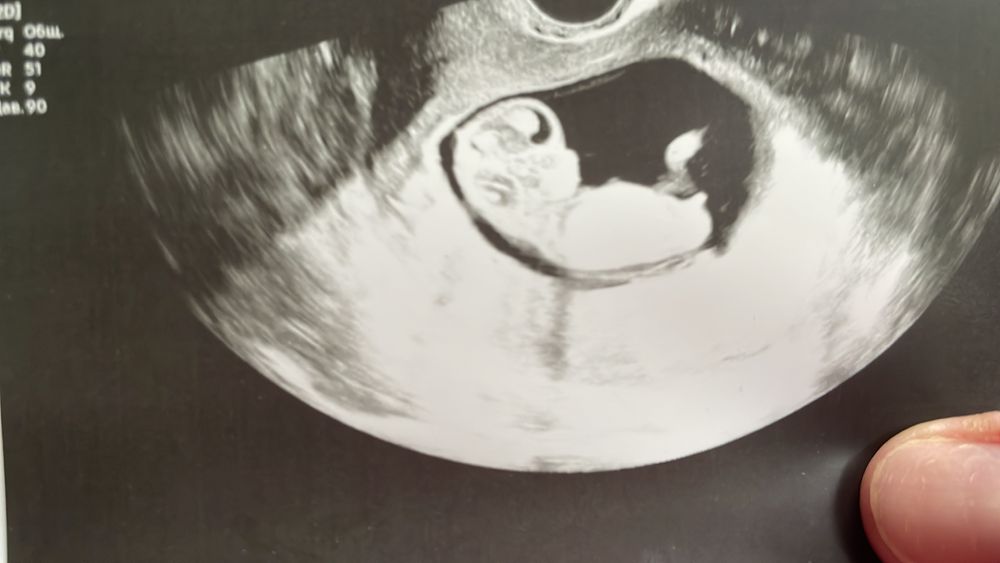

Девочки подскажите пол)))

Да, похож на мальчика, бугорок вверх.

Мне тоже кажется что мальчик, половой бугорок сильно вверх смотрит. ❤️

На 1 неделе половой бугорок выглядит +- одинаково у мальчиков и девочек, даже врачи еще не могут сказать Вам же врачи на узи, наверное, не сказали пол?) Если они не увидели опытным глазом, то тут точно по фото не дадут верный ответ)

Мальчик или девочка, 50:50. На вашем сроке половые органы недифференцированный, и половой бугорок занимает среднее положение-поэтому определение пола на УЗИ невозможно.